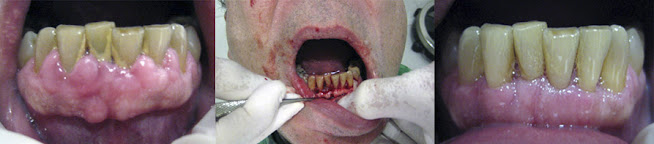

Las imágenes corresponden a un paciente sometido a una cirugía a colgajo, que incluyó remodelado del hueso alveolar y gingivoplastia, con el objetivo de tratar y frenar la progresión de la periodontitis, así como mejorar la estética del borde anterior de la mandíbula.

La cirugía a colgajo es el procedimiento más comúnmente realizado. Se utiliza para eliminar los depósitos de sarro en bolsas periodontales profundas o reducir su tamaño. Este procedimiento consiste en levantar las encías, eliminar el sarro, limpiar las raíces y el hueso, y luego reposicionar las encías mediante suturas. Con el tiempo, las encías sanarán y se ajustarán mejor alrededor de los dientes. Aunque los dientes pueden parecer más largos tras el tratamiento, esta apariencia es temporal, ya que su inserción en el hueso es lo que define la salud periodontal y la longevidad de los dientes.

La cirugía a colgajo es especialmente indicada cuando las bolsas periodontales se extienden más allá del límite mucogingival o cuando se requiere tratar lesiones óseas o alteraciones en las furcas de los molares. Una de las principales ventajas de este procedimiento es que preserva la encía existente y permite un acceso directo al hueso alveolar y las raíces, facilitando su limpieza mecánica con instrumentos quirúrgicos. Además, se pueden llenar los defectos óseos con osteointegradores, y finalmente, el colgajo se recoloca en su posición original o se desplaza apicalmente, adaptando el margen gingival a las condiciones locales.